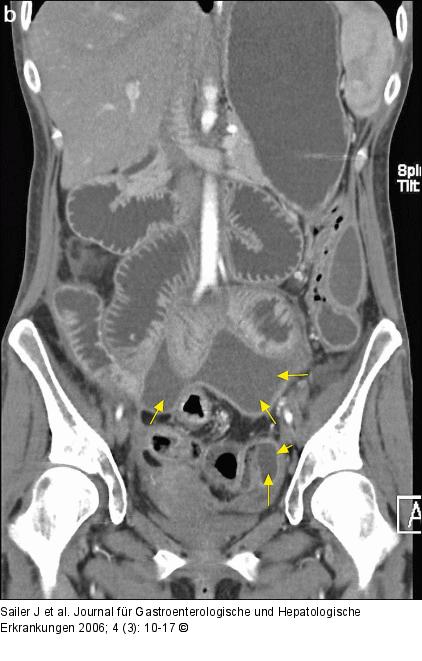

Abbildung 3a-b: CT-Enteroklysma CT-Enteroklysma einer 41jährigen Patientin, klinische Zeichen eines akuten Abdomens; axiale und coronale Rekonstruktionen: ausgedehnte, zwischen den Dünndarmschlingen gelegene Abszeßformation mit diskretem Rand-Enhancement (Pfeile), deutlich entzündliche Wandverdickung des terminalen Ileums (Pfeilspitzen). |

CT-Enteroklysma einer 41jährigen Patientin, klinische Zeichen eines akuten Abdomens; axiale und coronale Rekonstruktionen: ausgedehnte, zwischen den Dünndarmschlingen gelegene Abszeßformation mit diskretem Rand-Enhancement (Pfeile), deutlich entzündliche Wandverdickung des terminalen Ileums (Pfeilspitzen). |